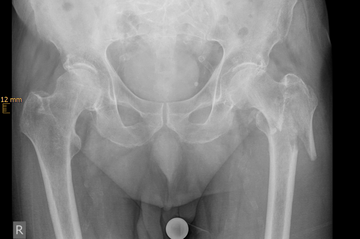

Ursache für komplexe Knochenbrüche wie Hüft- oder Schulterfraktur ist eine reduzierte Knochenqualität. Die häufigsten dieser Verletzungen sind die handgelenknahe Speichenfraktur (Radiusfraktur), die hüftgelenknahe Oberschenkelfraktur (mediale/pertrochantäre Fraktur), die Schulterfraktur (proximale Humerusfraktur) oder die Fraktur eines oder mehrerer Wirbelkörper.

Diese Verletzungen können für einen älteren Menschen teilweise gravierende Folgen haben. Eine Schenkelhalsfraktur kann bei einem älteren Patienten mit dem plötzlichen Verlust seiner Selbstständigkeit und Mobilität verbunden sein und eine Vielzahl anderer Komplikationen nach sich ziehen. Eine drohende temporäre oder dauerhafte Pflegebedürftigkeit kann sich daraus entwickeln.

Der verletzte ältere Mensch benötigt oft ein komplexes Behandlungsregime, das seine Unfallfolgen, die schlechte Knochenqualität (Osteoporose) und die Nebenerkrankungen (Multimorbidität) gleichermaßen einschließt.